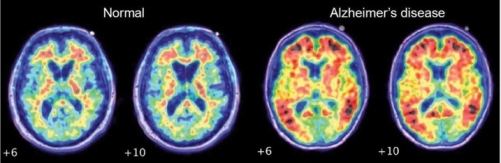

Many scientists believe that the disease is caused by aggregations of proteins in the brain. This theory, known as the ‘amyloid hypothesis’ states that strands of a protein, known as amyloid beta, clump together to form deposits known as amyloids. Over time, more proteins become stuck to these deposits, eventually forming plaques which are large enough to disrupt communication between cells in the brain. Immune cells are activated, causing inflammation and, ultimately, the destruction of brain cells.